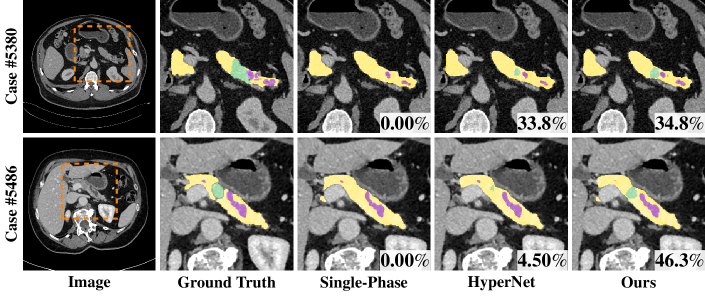

Refer to caption

Figure 1: Visual comparison of arterial and venous images (after alignment) as well as the manual segmentation of normal pancreas tissues (yellow), pancreatic duct (purple) and PDAC mass (green). Orange arrows indicate the ambiguous boundaries and differences of the abnormal appearances between the two phases. Best viewed in color.

Pancreatic ductal adenocarcinoma (PDAC) is the 4th most common cancer of death with an overall five-year survival rate of 8%. Currently, detection or segmentation at localized disease stage followed by complete resection can offer the best chance of survival, i.e., with a 5-year survival rate of 32%. The accurate segmentation of PDAC mass is also important for further quantitative analysis, e.g., survival prediction [1]. Computed tomography (CT) is the most commonly used imaging modality for the initial evaluation of PDAC. However, textures of PDAC on CT are very subtle (Fig. 1) and therefore can be easily neglected by even experienced radiologists. To our best knowledge, the state-of-the-art on this matter is [20], which reports an average Dice of 56.46%percent56.4656.46\%. For better detection of PDAC mass, dual-phase pancreas protocol using contrast-enhanced CT imaging, which is comprised of arterial and venous phases with intravenous contrast delay, are recommended.